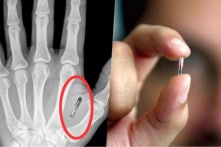

Trào lưu công nghệ ở Thụy Điển: Cấy chip vào bàn tay

Số người được cấy chip ngày càng tăng lên không đồng nghĩa với việc công nghệ này tốt cho tất cả mọi người